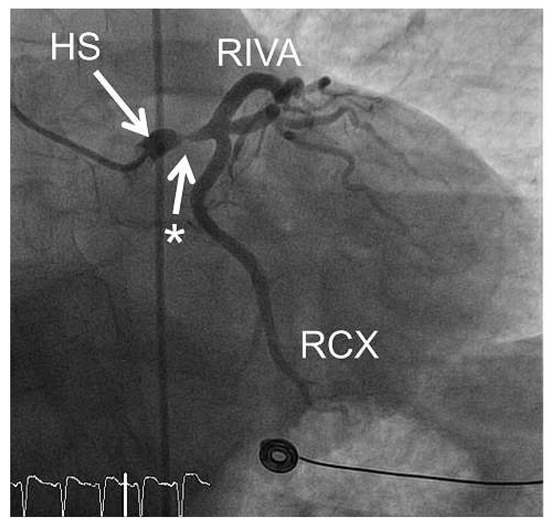

6 pages, 1978 KB

Article

Complex Percutaneous Coronary Interventions by Transradial Approach Using Sheathless Guiding Catheters

by Stephane Noble, Robert Francis Bonvini, Caroline Frangos, Pierre-Frédéric Keller and Marco Roffi

Cardiovasc. Med. 2012, 15(7), 218; https://doi.org/10.4414/cvm.2012.01682 - 29 Aug 2012

Cited by 1 | Viewed by 95

Abstract

Objective: To analyse our single centre experience with sheathless guiding catheters (GC) for complex percutaneous coronary interventions (PCI). Background: Failure of performing transradial approach (TRA) increases with the sheath size used, especially in cases of small and tortuous radial arteries. The [...] Read more.

Objective: To analyse our single centre experience with sheathless guiding catheters (GC) for complex percutaneous coronary interventions (PCI). Background: Failure of performing transradial approach (TRA) increases with the sheath size used, especially in cases of small and tortuous radial arteries. The use of recently developed sheathless GC may facilitate performance of TRA for complex PCI requiring large-lumen GC. Methods and results: We retrospectively analysed 20 consecutive patients who underwent complex PCI performed by TRA with a Sheathless Eaucath® GC (Asahi Intecc, Japan). The patients mean age was 68.9 ± 11.3 years. Indications for PCI were ST elevated myocardial infarction in 2 patients (10%), acute coronary syndrome in 4 (20%), and chronic stable angina in 14 (70%). Right TRA was used in all but one case. The 7.5-French (F) sheathless GC was used in all the procedures. Radial and brachial arteries crossing was possible in all cases with no associated procedural or GC-related complications. The number of vessels treated per patient was 1.30 ± 0.47 with 1.70 ± 0.92 stents implanted per vessel. The left main stem was the treated lesion in 9 patients (45%), 5 patients (25%) had complex bifurcation lesions and one (5%) had chronic total occlusion. The remaining 5 patients (25%) had severely tortuous and/or calcified coronary lesions. Rotablation was required in 2 procedures. Mean fluoroscopic time was 20.3 ± 7.5 min and mean volume of contrast media was 254 ± 83 ml. Conclusion: This preliminary experience in complex PCI, suggests that TRA using 7.5-F sheathless GC might be an attractive alternative to transfemoral access using 7-F conventional. Full article

Show Figures

Figure 1